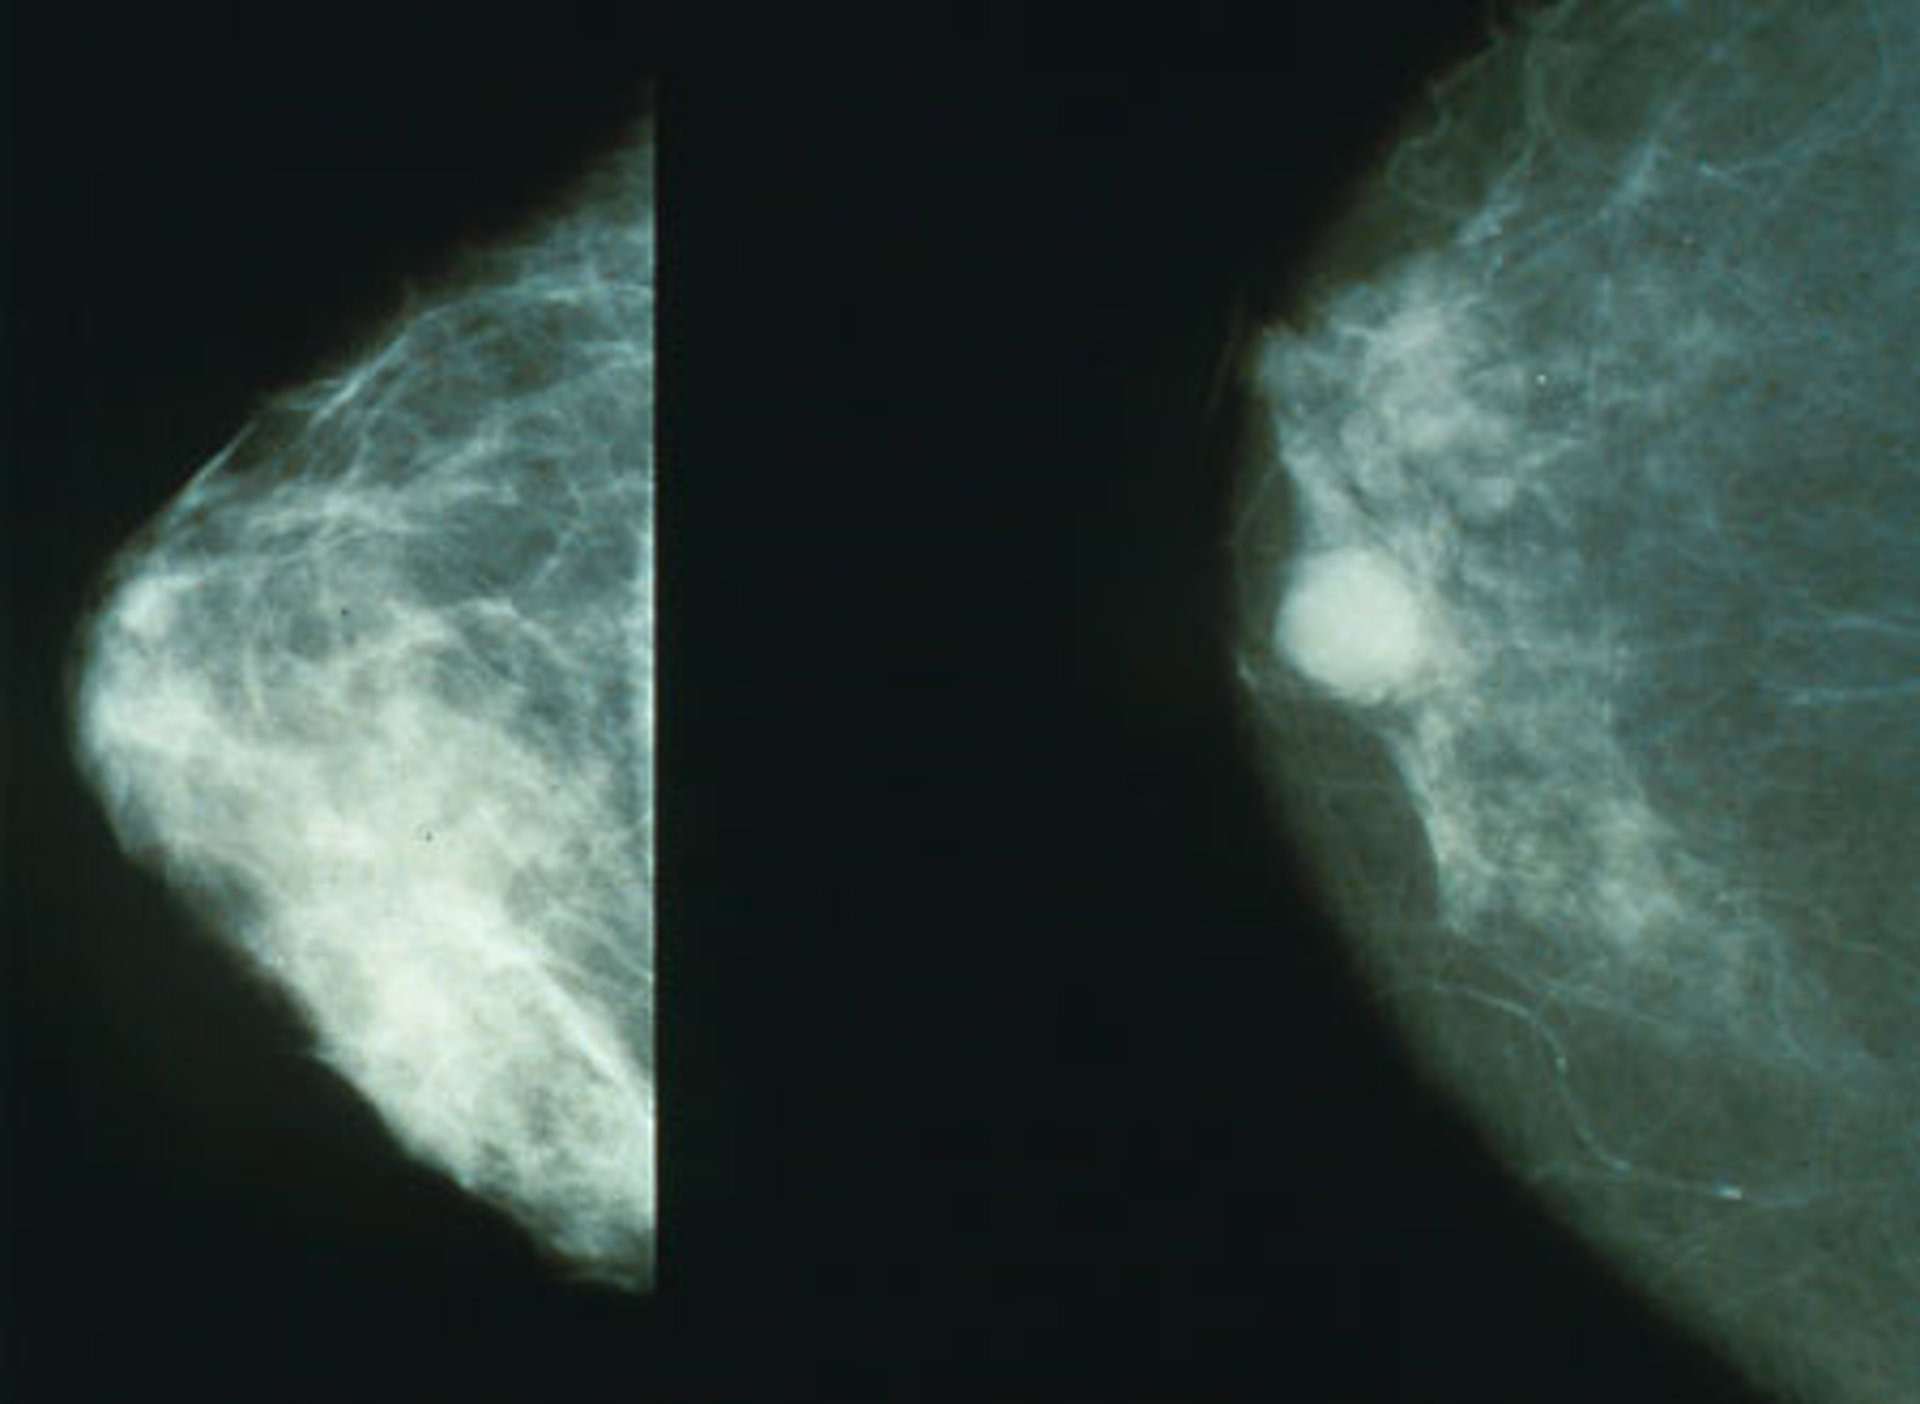

Las mejoras en la supervivencia se han producido por el progreso de los diagnósticos en etapas precoces de la enfermedad, los cribados mediante mamografías y las mejoras en los tratamientos.